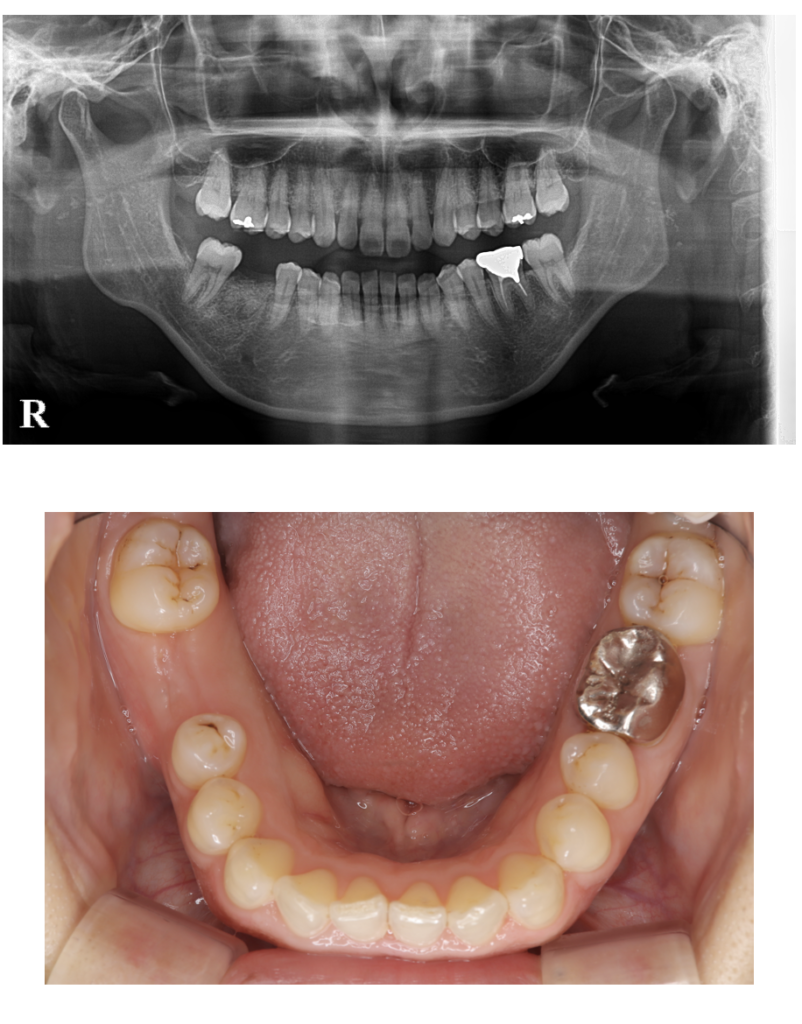

インプラント 13 No.85

Before

After

| 備考 | 院長より インプラントは自分の歯のように噛むことが出来ます奥歯が一本なくなっただけで噛みにくくなる方もいらっしゃいます。インプラント埋入オペ後、粘膜の治癒を待つときに、このようなキャップを使用することもあります。 |